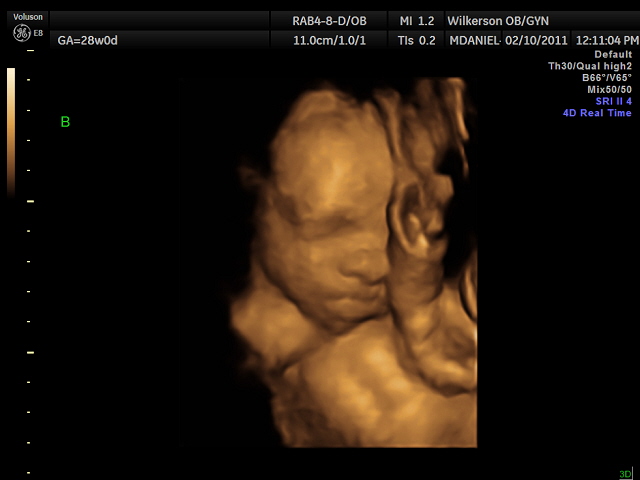

We had our 4-D ultrasound today. James would not cooperate at all but Jackson did. He was so precious he kept his hand over his face though. It was so neat. They are definitely cramped in there. We go back Monday and hopefully James will work with us. Here our a few pictures we have more but they are video rather than pictures.

Here is sweet Jackson: